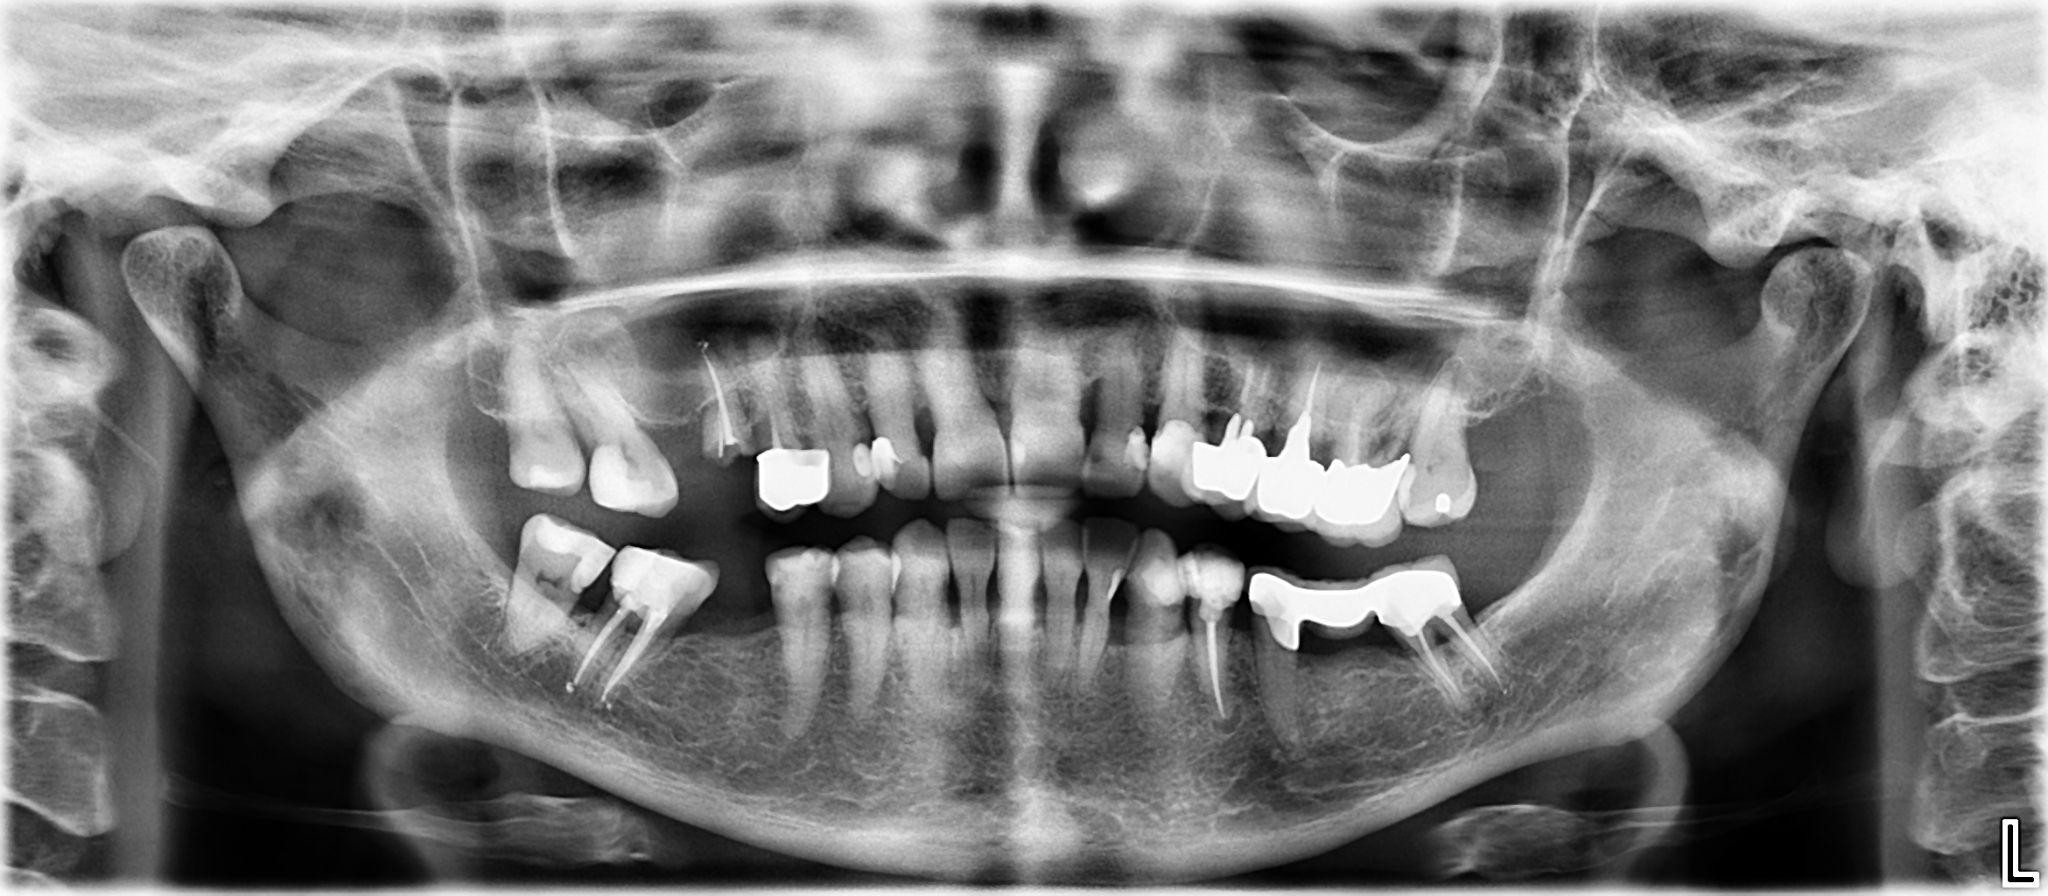

1. What option cannot be selected for the first quadrant of this panoramic X ray?

2. What option cannot be selected for the second quadrant of this panoramic X ray?

3. What option can be selected for the third quadrant of this panoramic X ray?

4. What option cannot be selected for the forth quadrant of this panoramic X ray?